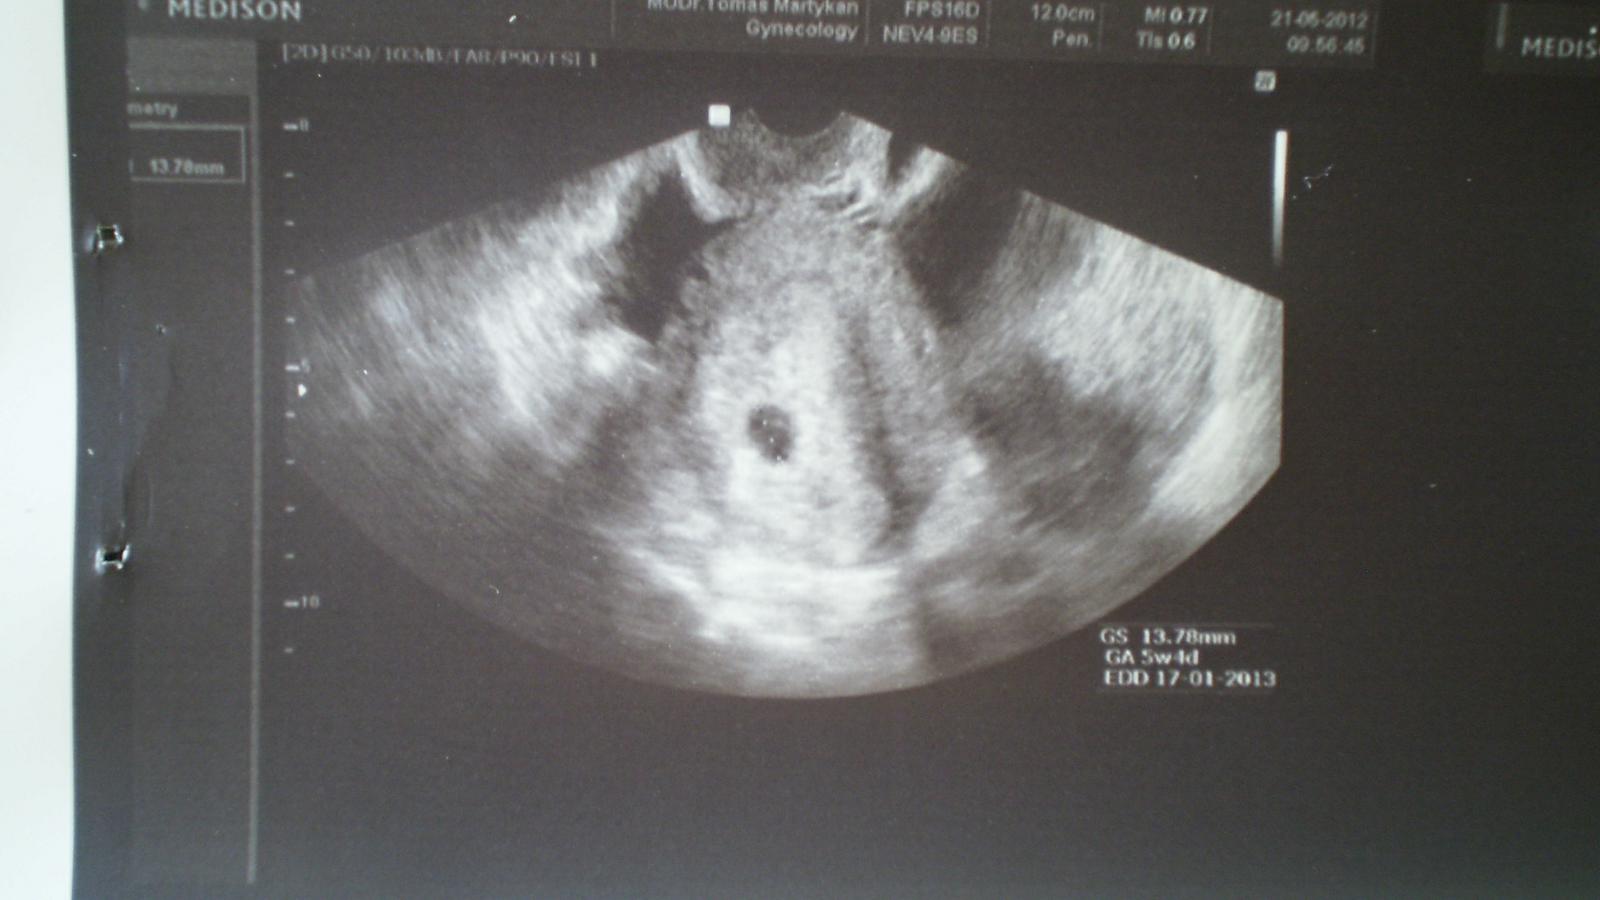

Dívky, tak jsem si došla na gyndu, páč jsem dívka zvědavá a chtěla jsem vědět, kolik tam té drobotiny mám a zda je všechno v pořádku... MUDr. mi udělal utz a...jsem 5+4tt, mám jeden gestační váček a TT mi stanovil na 17.1.2013 😵 😵 😵 Stále nemůžu uvěřit, že ten zázrak, něco tak malého, tak vysněného, v sobě už mám.... 😵